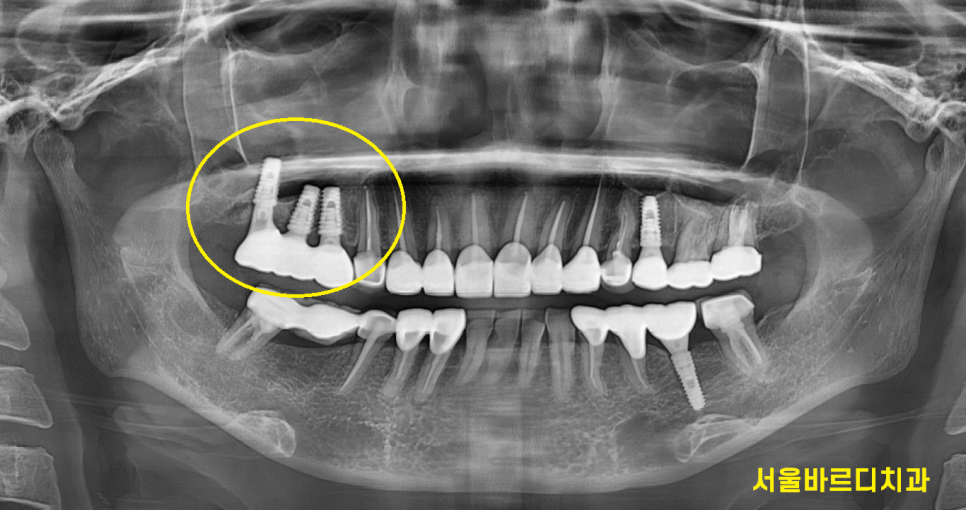

230814

맨 처음 저희 병원 오셨을 때부터

뿌리쪽 충치도 보이고

치아가 안좋지만 뽑기에는 아까우니

쓸 때까지 쓰라고 말씀드렸던 부분입니다.

겉으로 눈으로 보기에는 멀쩡해보이는데

x-ray를 찍으면 다 보입니다~

240313

머리 부분이 아주 조금만 남아있죠?

240415

발치 후 임플란트를 해주었습니다.

기존에는 치아 1개가 없지만

양 옆 치아를 깎아서 보강해준 브릿지 형태였지만

이번에는 부러지거나 탈나지 않게

임플란트 치료로

모자른 개수 없게 치아 원래 개수대로

만들어주었습니다.